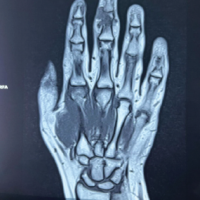

Six months after traumatism, magnetic resonance imaging was performed and showed no sign of avascular necrosis of the radial head (Fig. 3). The range of motion was still limited at that time, with a 30° lack of elbow extension and pronation limited to 20°. Radiograph showed persisting slight anterior subluxation of the radial head. A night dynamic elbow extension brace (Ultraflex) was applied to improve extension.